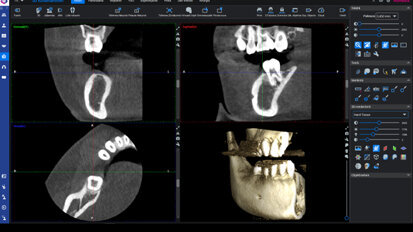

Rehabilitace Straumann